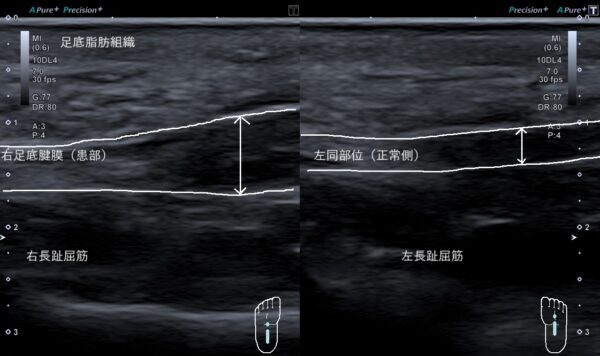

超音波画像観察を行うと右足底腱膜が、左と比較して厚みが増して太くなっていました(画像、矢印の長さの比較)。

しかし、会社員は日頃から2万歩以上歩いていることや階段を駆け上がったことで足底腱膜に負担がかかり過ぎ、足底腱膜が肥厚、太くなってアーチのばねの伸び縮みが働かなくなって、足底腱膜の組織が傷ついて痛みが出てしまったと考えられます。